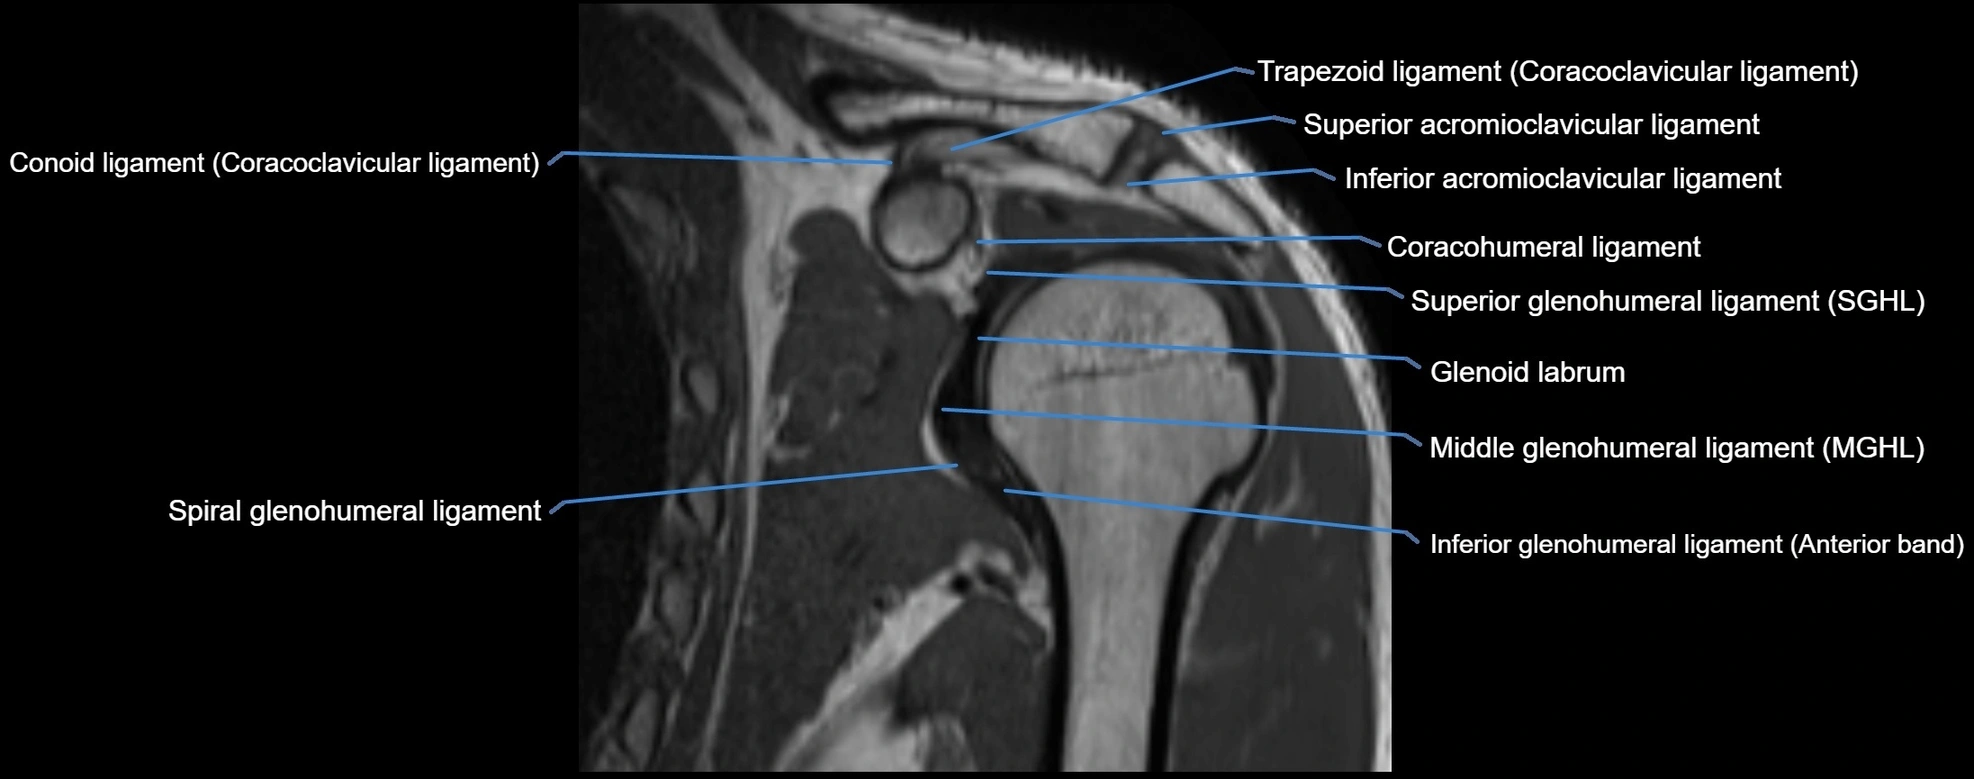

MRI Appearance

• T1-weighted images:

• Normal ligament: Low signal (dark linear band) spanning acromion to clavicle.

• Surrounding fat planes: Bright, delineating the ligament clearly.

• Marrow of clavicle and acromion: Bright due to fatty content.

• Tears: Discontinuity or irregular thickening with intermediate-to-bright signal.

• Chronic injury: Thinning, fraying, or irregular low-signal fibers with adjacent scarring.

• T2-weighted images:

• Normal ligament: Low signal, homogeneous.

• Partial tear or sprain: Focal hyperintensity or thickening.

• Complete tear: Discontinuity with fluid-bright gap between clavicle and acromion.

• Associated edema: Bright signal in distal clavicle or acromion marrow.

MRI images

image